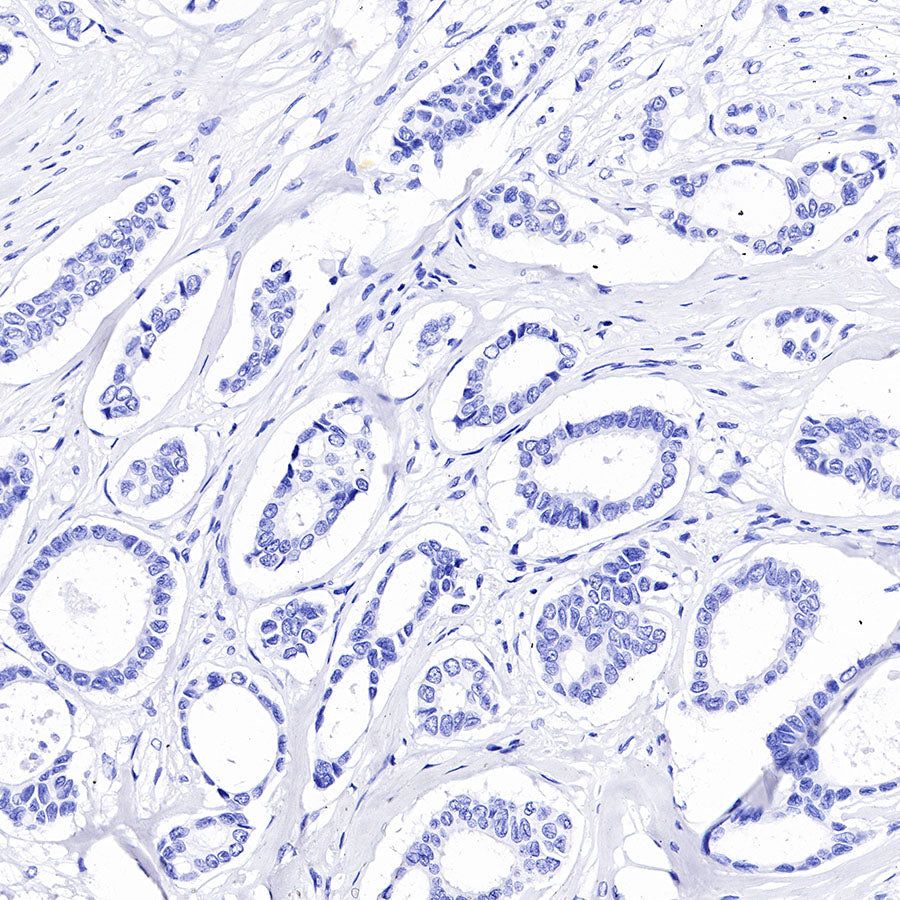

IHC shows positive staining in paraffin-embedded human colon cancer. Anti-GPA33 antibody was used at 1/2000 dilution, followed by a HRP Polymer for Mouse & Rabbit IgG (ready to use). Counterstained with hematoxylin. Heat mediated antigen retrieval with Tris/EDTA buffer pH9.0 was performed before commencing with IHC staining protocol.